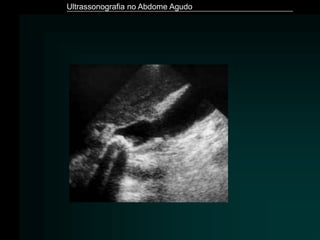

Colecistite Aguda

– Principal condição aguda da vesícula biliar

– 90 - 95% obstrução do colo vesicular ou no ducto cístico por

cálculo

– US é o método de imagem de escolha

– Achados Ecográficos

» Presença de colelitíase

» VB distendida (diâmetro transverso > 4 cm)

» Espessamento da parede da vesícula (>3 mm)

» Aspecto lamelar da parede

» Perda de definição da parede

» Sinal de “Murphy Ultrassonográfico”